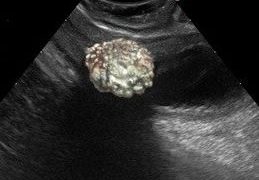

季節性牧草由来筋症(SPM)としても知られる非定型筋症(AM)は、シカモアの種子、和名はスズカケノキまたはシカモアの実生を食べることによって引き起こされる馬の致命的な病気です。セイヨウカジカエデまたはトネリコバノカエデの種子にはヒポグリシン...